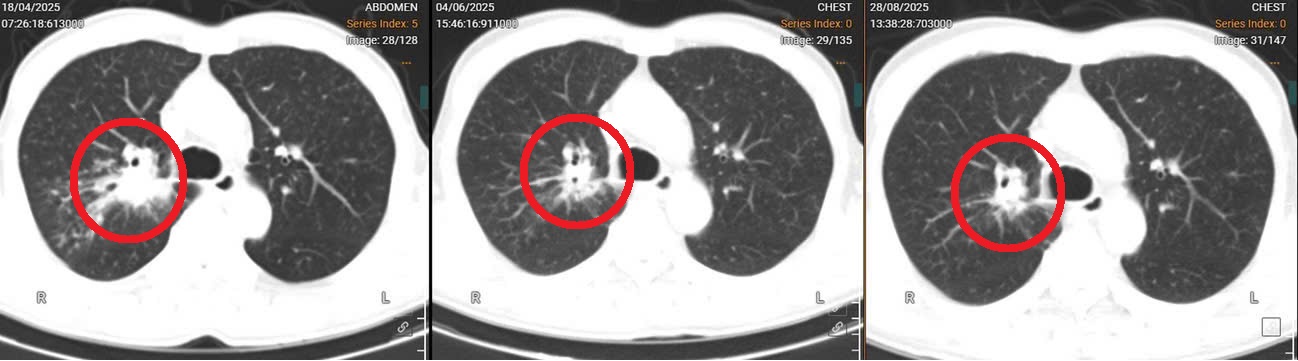

Người bệnh nhập viện trong tình trạng ho nhiều, đau tức ngực. Hình ảnh CT phổi cho thấy u thùy trên phổi phải, nhiều nốt vệ tinh phổi phải và trái, hạch trung thất phải ~1-1,5cm, PET CT hình ảnh bắt FDG tương tự. Dựa vào kết quả xét nghiệm gen của người bệnh có chỉ số phù hợp với miễn dịch, bác sĩ đã đưa ra phác đồ điều trị kết hợp hai liệu pháp hóa trị và miễn dịch.

Sau chu kỳ điều trị đầu tiên, người bệnh có nhiều cải thiện lâm sàng, hết đau, không khó thở và không phải dùng đến thuốc giảm đau. Quá trình điều trị, người bệnh đáp ứng với thuốc tốt, hệ miễn dịch cơ thể tăng, người bệnh trở lại sinh hoạt gần như bình thường. Tiếp tục điều trị các chu kỳ tiếp theo, người bệnh dung nạp thuốc tốt và không gặp phải độc tính, tác dụng phụ của thuốc. Kết quả CT phổi cho thấy khối u phổi đã giảm kích thước đáng kể.

Hình ảnh phim chụp CT phổi cho thấy kích thước khối u của người bệnh đã giảm dần sau các chu kỳ điều trị